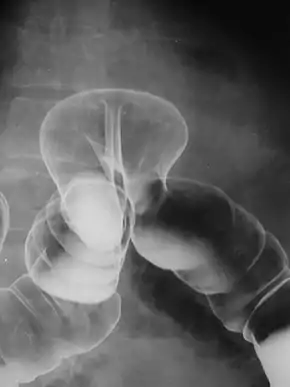

By far the most common hernias (up to 75% of all abdominal hernias) are the so-called inguinal hernias. Inguinal hernias are further divided into the more common indirect inguinal hernia (2/3, depicted here), in which the inguinal canal is entered via a congenital weakness at its entrance (the internal inguinal ring), and the direct inguinal hernia type (1/3), where the hernia contents push through a weak spot in the back wall of the inguinal canal. Inguinal hernias are the most common type of hernia in both men and women. In some selected cases, they may require surgery. There are special cases in which the hernia may contain both direct and indirect hernia simultaneously pantaloon hernia, or, though very rare, may contain simultaneous indirect hernias.[15]

Pantaloon hernia (Saddle Bag hernia) is a combined direct and indirect hernia, when the hernial sac protrudes on either side of the inferior epigastric vessels.